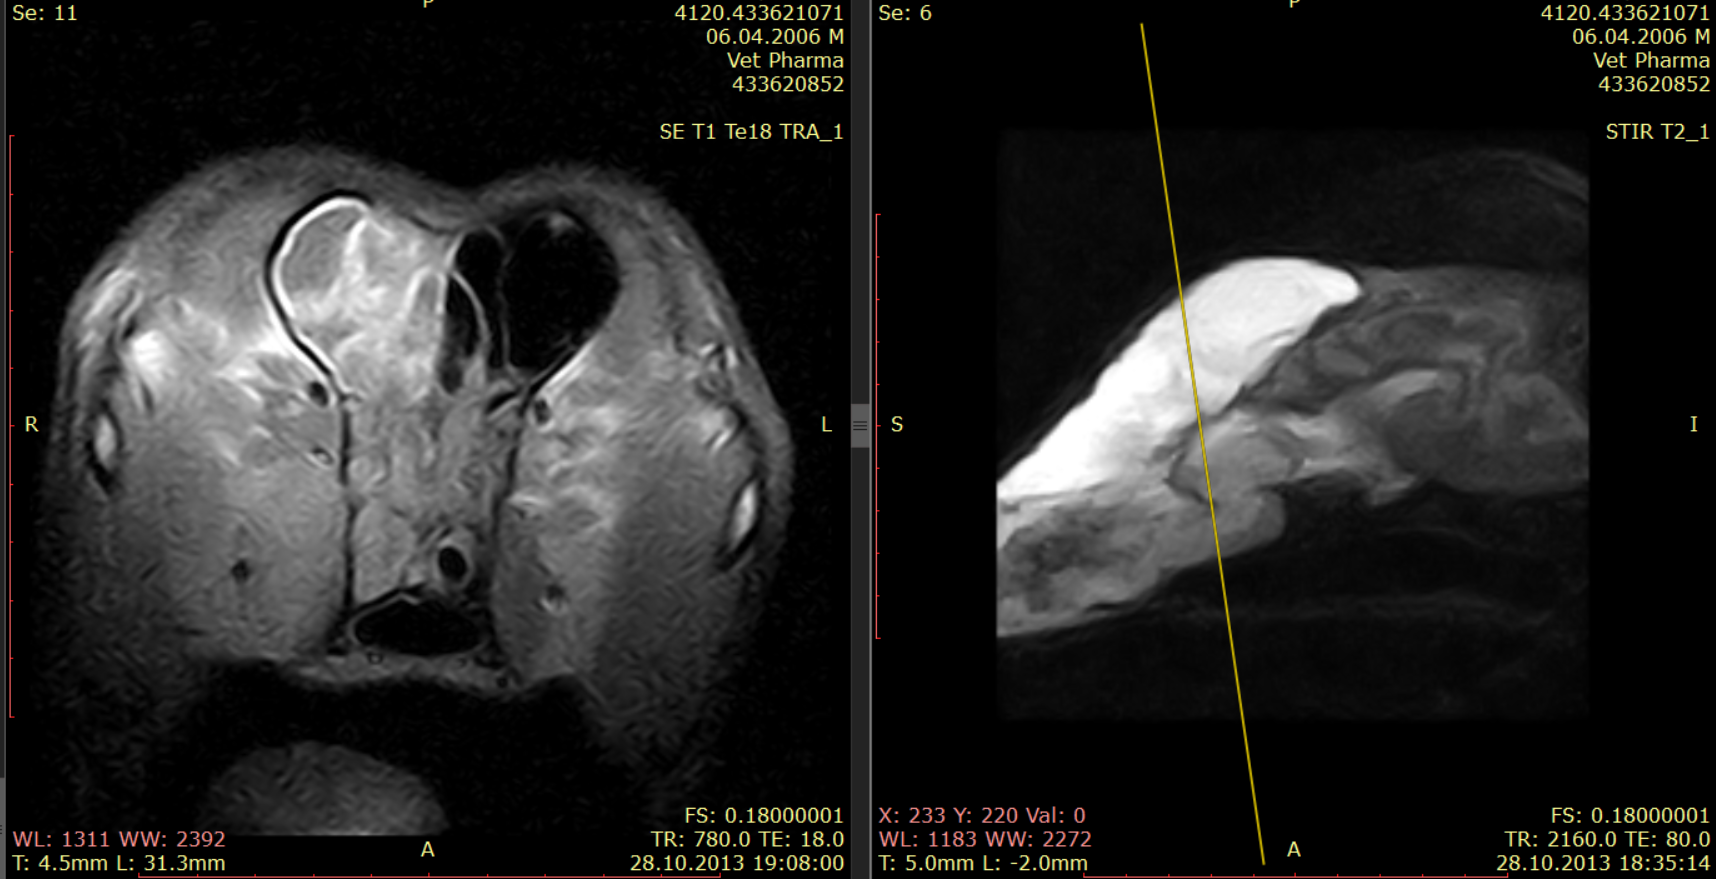

Магнитно-резонансная томография или компьютерная томография носовых ходов и придаточных пазух считаются золотым стандартом визуальной диагностики опухолей носовой полости. Для планирования лечения необходимо определить локализацию новообразования.

Объем новообразования и размер перифокального отека имеют значение для прогноза. Оценить по компьютерной томографии такие параметры, как размер новообразования и отек вокруг опухоли, нельзя.

Рис. 4. Программа FLAIR. Перифокальный отек обозначен стрелками, при этом объем новообразования на следующем рисунке 5 гораздо меньше (обозначено стрелками).Рис. 5. Программа T1 с контрастом.

Рис. 4. Программа FLAIR. Перифокальный отек обозначен стрелками, при этом объем новообразования на следующем рисунке 5 гораздо меньше (обозначено стрелками).Рис. 5. Программа T1 с контрастом.

Рис.6. Та же собака, что на рис. 5 и 4.

Рис.6. Та же собака, что на рис. 5 и 4.

Рис. 7.

Рис. 7.